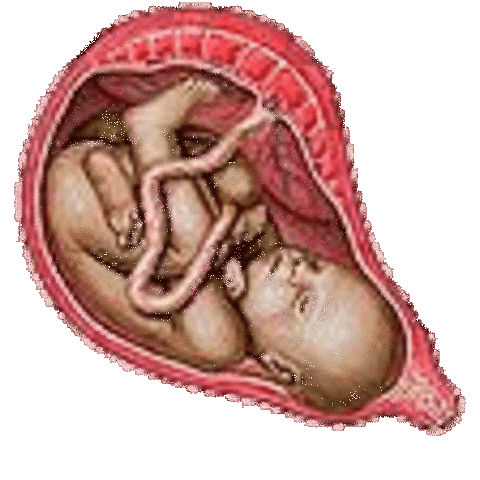

week 35

Babys reflexes are coordinated. Lungs are fully developed.

• week 36

week 36

May feel contractions of the womb. Baby is becoming chubby as fat layers build.